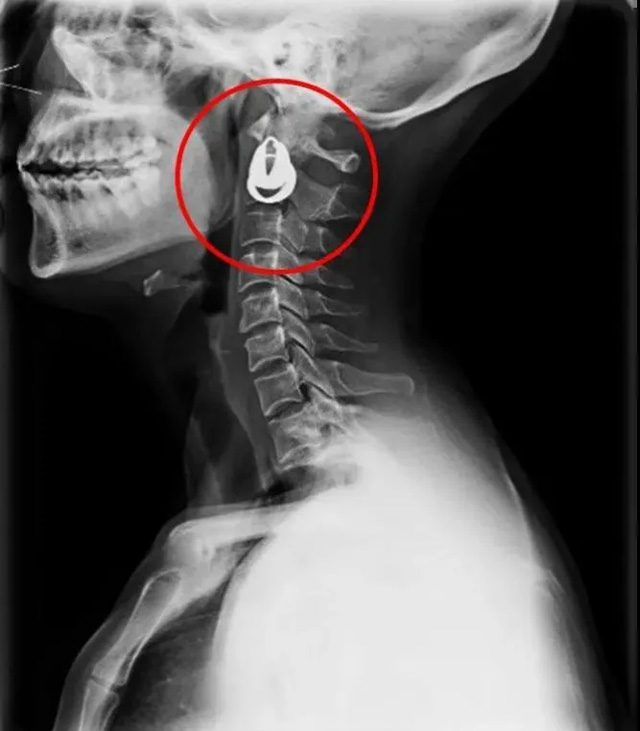

DR是一種比較常規(guī)的基礎(chǔ)影像學(xué)檢查方式,適用于人體各部位的健康普查及疾病檢查等優(yōu)勢(shì),在臨床基礎(chǔ)檢查中備受醫(yī)生和患者的青睞。DR體檢車在健康體檢中有著非常重要的地位,由通過電纜串接在一起的探測(cè)板、掃描控制器、系統(tǒng)控制及影像顯示器等構(gòu)成。對(duì)比CT檢查而言,DR檢查的價(jià)格更低,輻射劑量更小它可以讓疾病預(yù)防,微細(xì)病變可更好顯示診斷治療提供科學(xué)的結(jié)果依據(jù)。很多外傷患者都要做DR檢查,來判斷是否骨折或其他的情況。體檢過程中面對(duì)DR體檢車做檢查時(shí)候需要準(zhǔn)備注意什么呢?很多時(shí)候大家都有這樣的疑問,身上攜帶的物品是否會(huì)對(duì)圖像造成遮擋或給機(jī)器帶來干擾?檢查前如何準(zhǔn)備才不會(huì)影響檢查準(zhǔn)確性?